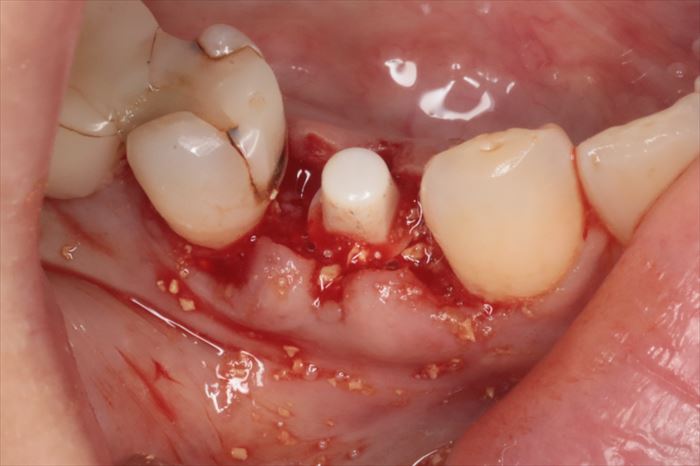

骨の陥凹部分に骨移植材を填入して膨らみが出ました。

骨となって治癒していきます。

今後の骨吸収を防ぐための予防的な骨増生処置という概念です。

抜糸不要な吸収性縫合糸で垂直マットレス縫合しました。

埋入トルクは十分なことから6週後に仮歯を作成して噛めるようになります。

インプラントのネック部分をカバーするように粘膜を寄せて縫合しています。